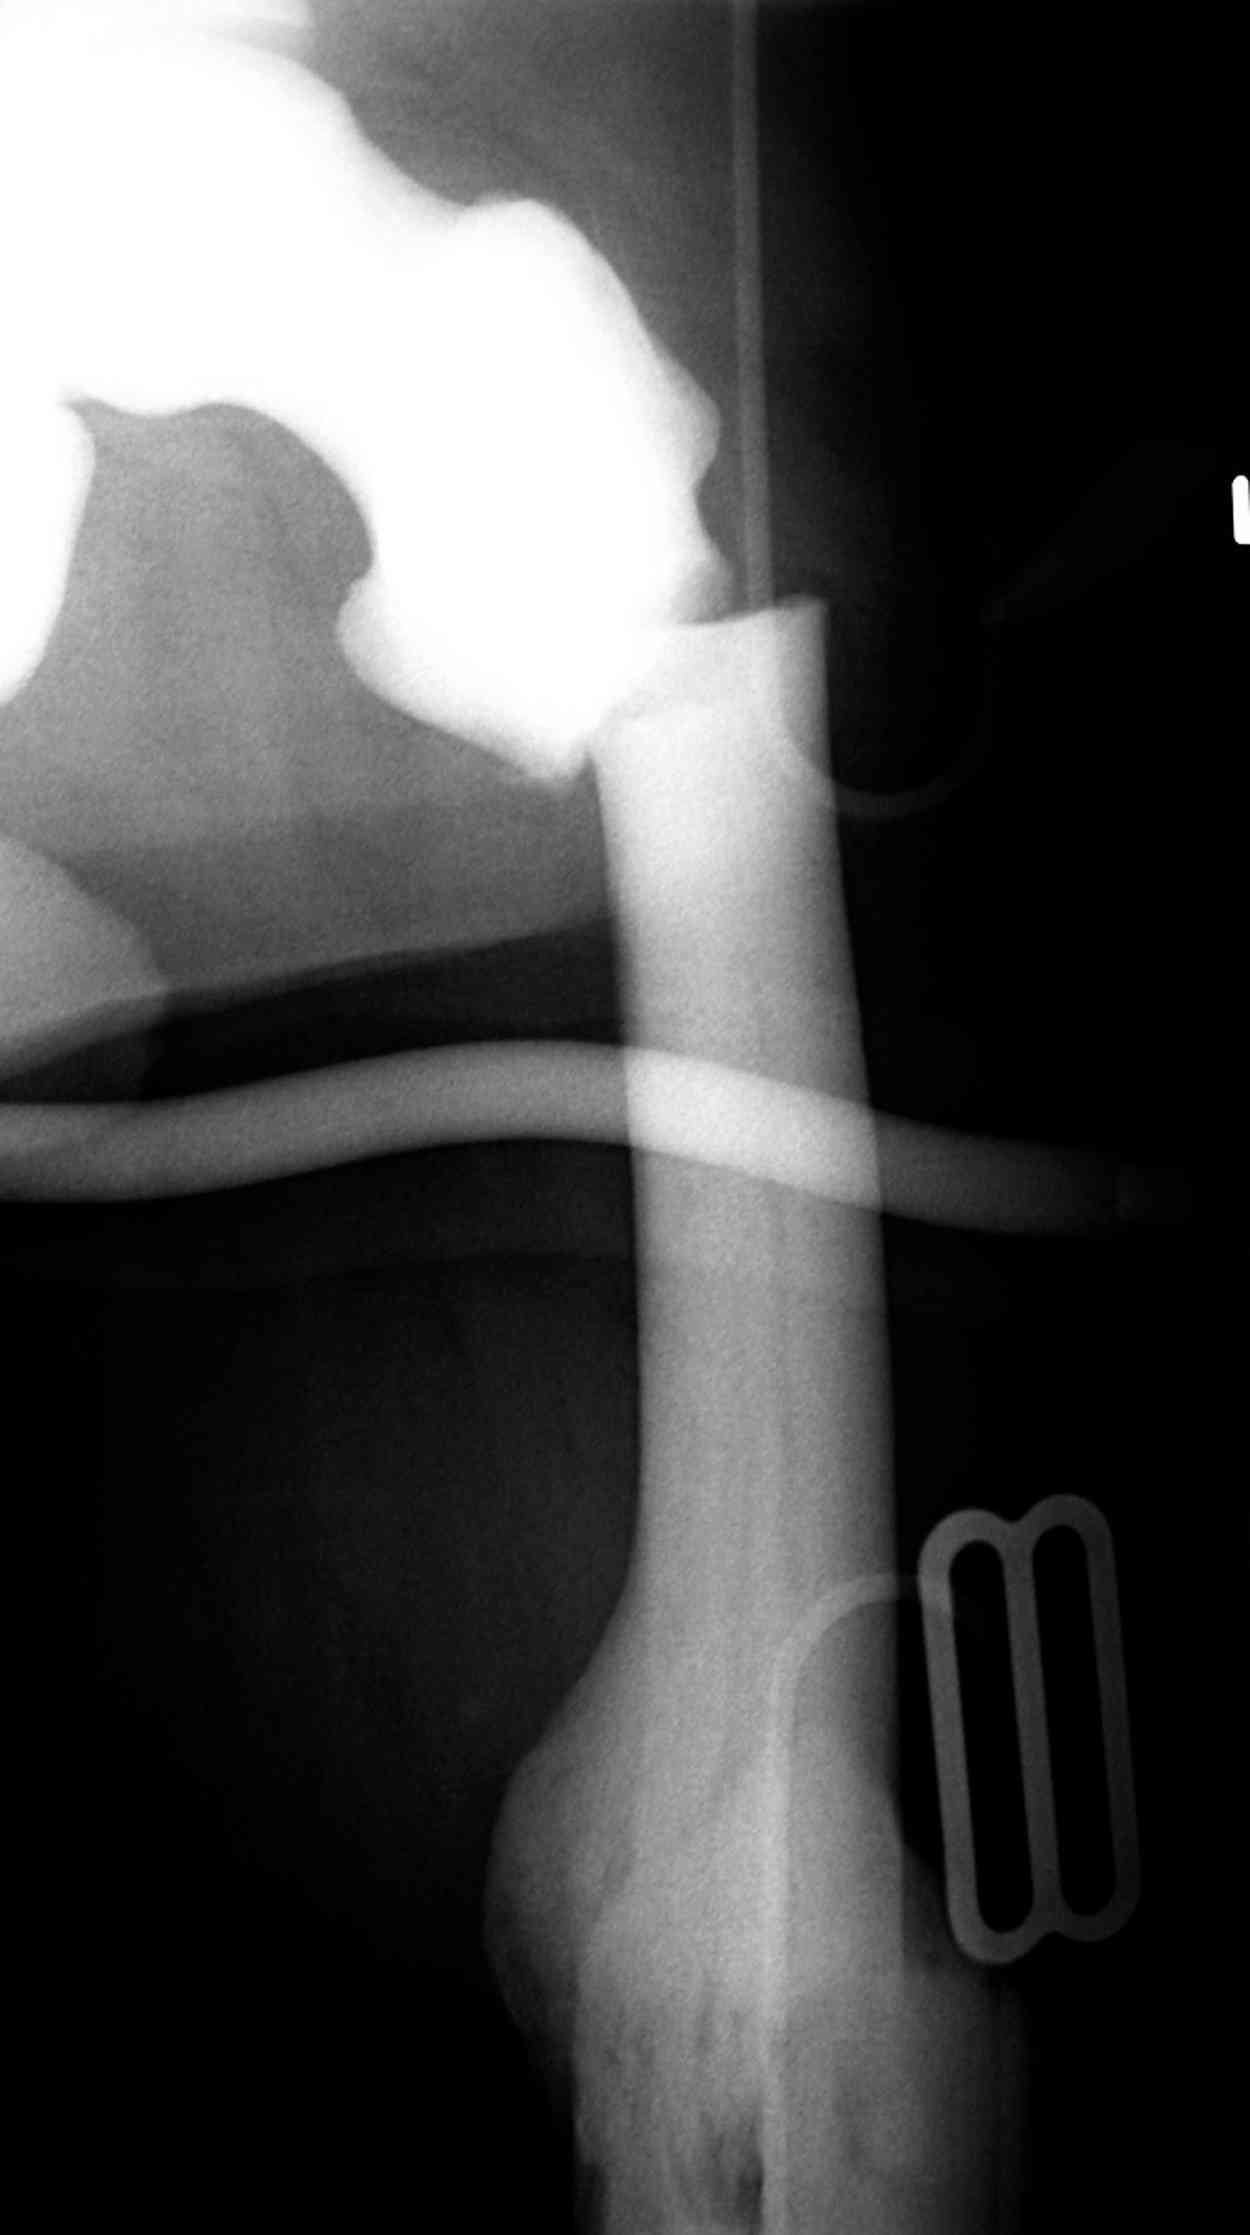

Не вызывает ли подозрение, что отсутствует медуллярный канал, как просверлить канал?

Канал, возможно, действительно запаян. Но разве большие проблемы его создать и рассверлить (если только это мраморная болезн?) Уверен, в вашей клинике есть для этого всё.

Djoldas Kuldjanov >как просверлить канал?

1. Верхушку б\вертела всктыть спицей и рассверлить каннюлированным инструментом (14 мм).

2. Если в диафизарной части канал запаян, то, используя сам штифт, введенный в проксимальный отломок, как центратор, по нему завести спицу в центр дистального отломка и сформировать канал, сначала тонкий 4 мм.

3. Гибкими (неканнюлированными) развертками диаметром 6,7 и 8 мм последовательно расширить канал.

4. Рассверливать каннюлироваными развертками по направляющей спице до нужного диаметра.

После неудачной попытки скелетного вытяжения в первом мед.учреждении, после осмотра снимков и изучения истории, поставили диагноз “Остеопетроз” или мраморная болезнь, редкая наследственная костная паталогия, где имеется нарушение формации остеокластов.